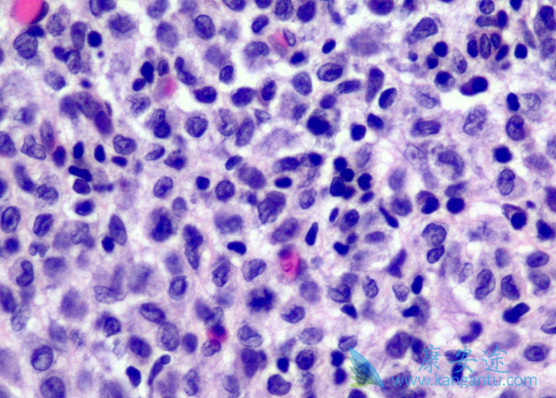

Erdheim-Chester 病(ECD)为一种罕见的非朗格罕组织细胞增生症,其中心脏与神经系统受累,与死亡率与发病率的显着增加相关。研究显示超过一半的 ECD 患者有 BRAFV600E 突变。威罗菲尼(Vemurafenib),是一种选择性低分子量 BRAF 激酶抑制剂,可以选择性抑制表达 BRAFV600E 突变蛋白的肿瘤细胞增殖,对转移性黑色素瘤(包括脑内转移)有效。

有研究显示,威罗菲尼对 3 名 ECD 伴 BRAF 突变患者高度有效。而本文报道了一例威罗菲尼有效治疗鞍上病变压缩视交叉神经导致视力减退的 ECD 患者。但这是一个单一的观察性研究,没有对照试验。在病人签署知情同意书后,开始使用威罗菲尼片治疗,具体剂量为 480mg(每天 2 次)。在第十天,两侧视力改善(左眼:0.7 升至 1.0;右眼:0.8 升至 1.0);双侧视野正常。通过 PET以及脑 MRI 对患者重新进行评估。PET 显示鞍上仅存有轻微残留;肺代谢亢进;MRI 检测显示肿瘤尺寸降低。最后在治疗期间没有副作用。

本次病例提示,BRAF 抑制治疗对中枢神经浸润性 ECD 患者有效。患者视力以及视野显着改善,并且快速回到正常水平。因此抑制 BRAF 激酶突变的药物,有可能成为威胁生命性 ECD 的一线治疗药物。尽管威罗菲尼(Vemurafenib)良好耐受;但仍应该考虑安全问题;尤其是长期治疗的效果。今后应该进一步评估 BRAF 抑制剂长期治疗的预后。